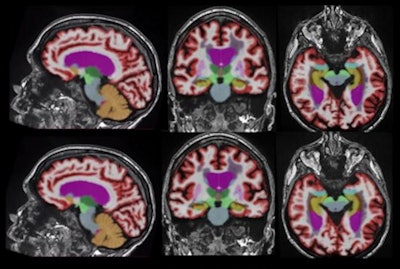

Representative 3D T1-weighted multiplanar images with volumetric segmentation on a 3-tesla scanner. [Left to right]: Sagittal, coronal, and axial T1-weighted images with standard protocols (scan time, five minutes and 44 seconds) on the top row and deep learning-enhanced accelerated imaging (scan time, two minutes and 18 seconds) on bottom row. Images courtesy of Dr. Suzie Bash.Next, a neuroradiologist classified the cases into clinical disease categories (normal/MCI or Alzheimer's disease), Bash said. The concordance of image biomarkers -- hippocampal occupancy score, hippocampi volume, superior lateral ventricles volume, and inferior lateral ventricles volume -- was also assessed for both sets of images.